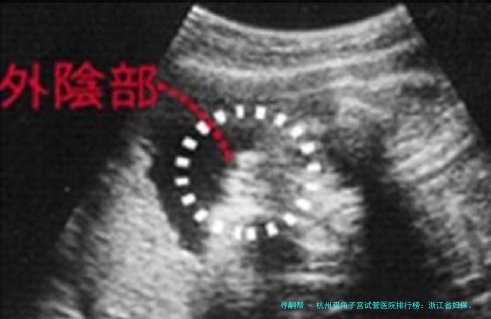

对于患有双角子宫的女性来说,生育之路往往充满挑战。双角子宫是一种子宫形态发育异常,可能影响胚胎着床和妊娠保持。在杭州,寻求专业的辅助生殖技术帮助成为了众多家庭的希望。本文将基于要地本地医疗资本、专家实力及患者反馈,梳理杭州地区在双角子宫试管婴儿范畴表现突出的医疗机构,并提供相关的医生与费用信息,为有这个需求的朋友提供一份切实的对照手册。

双角子宫并非不能自孕,但因其宫腔模样特殊,流产率、早产率相对较高。当自然受孕频频失利或存在其他不孕要素时,试管婴儿技术(IVF)便成为一个主要的抉择。杭州的辅助生殖医学中心于此类难题病例的处理上积累了丰富的经验,重点在于:

个性化的方案订定:根据双角子宫的具体样子(完全或不十足双角)、合并的其他问题(如输卵管、内分泌问题)来促排卵和移植方案。

严密的孕期监护:成功妊娠后,须要更紧密的监测为避免早产等合并症。